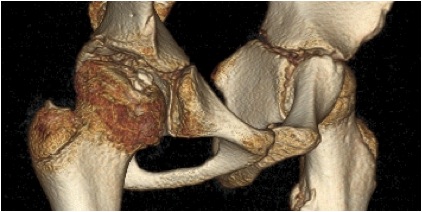

CT

Pathology

Head

Various areas of necrosis / revascularisation

- reossification from periphery

- typically anterior & lateral

Head deformity secondary to collapse

- biological plasticity during creeping substitution

- head subjected to uneven & excess forces

- flattening or saddle deformity

- anterolateral extrusion of cartilage

Coxa Magna

- flattening of head with lateral extrusion of physis + periosteal new bone